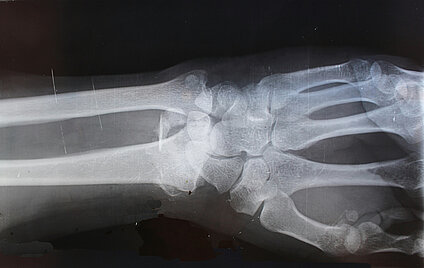

Aussagekräftige Daten aus einer aktuellen randomisierten kontrollierten Studie (RCT) bestätigen die Vorteile der Ultraschalldiagnostik (Fraktursonografie) bei Verdacht auf Brüche an den langen Armknochen bei Kindern: Mithilfe von Ultraschall lassen sich Knochenbrüche am Unterarm und in Nähe des Ellenbogens verlässlich und ohne funktionelle Nachteile genauso gut erkennen wie durch Röntgendiagnostik – und das ohne Strahlenbelastung.

(08.01.2023) Dank der guten zusätzlichen Evidenz aus der RCT, die zur Auswertung für den Vorbericht noch nicht vorlag, sieht das Institut für Qualität und Wirtschaftlichkeit im Gesundheitswesen (IQWiG) im nun vorliegenden Abschlussbericht sogar einen Beleg für einen höheren Nutzen der Fraktursonografie am distalen Unterarm, also die höchste Nutzenkategorie. Für Brüche am Ellenbogen bleibt es wie im Vorbericht beim Hinweis auf einen höheren Nutzen im Vergleich zur Strahlendiagnostik, weil dazu keine weitere Evidenz vorlag.

Die Vorteile und Nachteile von Ultraschalldiagnostik bei Verdacht auf Brüche an Oberarm, Ellenbogen oder Unterarm bei Kindern im Vergleich zur konventionellen Röntgenuntersuchung hat das IQWiG im Auftrag des Gemeinsame Bundesausschusses (G-BA) bewertet mit dem Fazit: An Unterarm und Ellenbogen kann die Fraktursonografie die konventionelle radiologische Diagnostik ersetzen. Dies erleichtert die Untersuchung für alle Beteiligten – Kinder, Angehörige und medizinisches Personal.

Kinder sind strahlenempfindlicher als Erwachsene und Knochenbrüche kommen bei ihnen häufiger vor: Nur etwa die Hälfte der Kinder erlebt keinen Knochenbruch während der Wachstumsphase. Solche Verletzungen sind überdies meist mit Schmerzen und Angstgefühlen verbunden – deshalb kommt es bei Kindern besonders auf eine möglichst einfache Untersuchungssituation und das Minimieren von Strahlenbelastung an. Die Fraktursonografie kommt ohne Strahlenbelastung aus und lässt sich in einer schmerzarmen Armhaltung durchführen, ohne dass sich die beunruhigten Kinder von den Eltern trennen müssen. Eine Röntgenuntersuchung wird dann nur noch notwendig, wenn das Ultraschallergebnis nicht eindeutig ist.